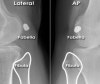

- 종자뼈(Fabella) : Anormal sesamoid bone of the lateral head of gastrocnemius tendon(Not to be mistaken for a fracture or loose body)